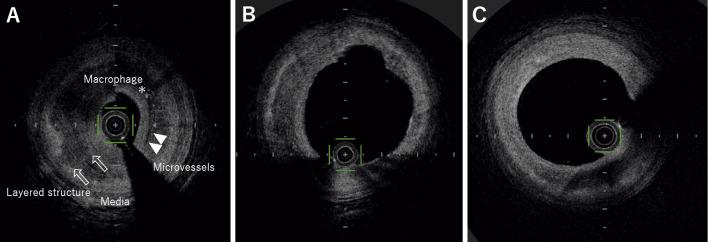

A 46-year-old man complained of chest pain at rest for the past three months. His symptoms gradually exacerbated and were suspected of being due to unstable angina. A coronary angiogram revealed focal tight stenosis at the proximal left anterior descending coronary artery with gross spastic coronary findings. Optical coherence tomography (OCT) revealed layered low-intensity structures with microvessels and the accumulation of macrophages, which indicated progressive stenosis with multiple-layered organized thrombus caused by coronary erosion. We treated the stenosis using a drug-coated balloon instead of drug-eluting stents. There was no restenosis, and OCT revealed good plaque healing at follow-up. This case suggests that the pre-interventional OCT plaque morphology can have a positive impact on the revascularization strategy.

一位 46 岁男性因过去三个月静息时胸痛而就诊。他的症状逐渐加重,疑似不稳定型心绞痛。冠状动脉造影显示左前降支近段局灶性严重狭窄,伴有明显的痉挛性冠状动脉改变。光学相干断层扫描(OCT)显示,伴有微血管和巨噬细胞聚集的分层低强度结构,提示由于冠状动脉侵蚀导致进行性狭窄和多层有组织的血栓形成。我们使用药物涂层球囊而非药物洗脱支架治疗狭窄。没有再狭窄,OCT 显示随访时斑块愈合良好。该病例提示,介入前 OCT 斑块形态可对血运重建策略产生积极影响。